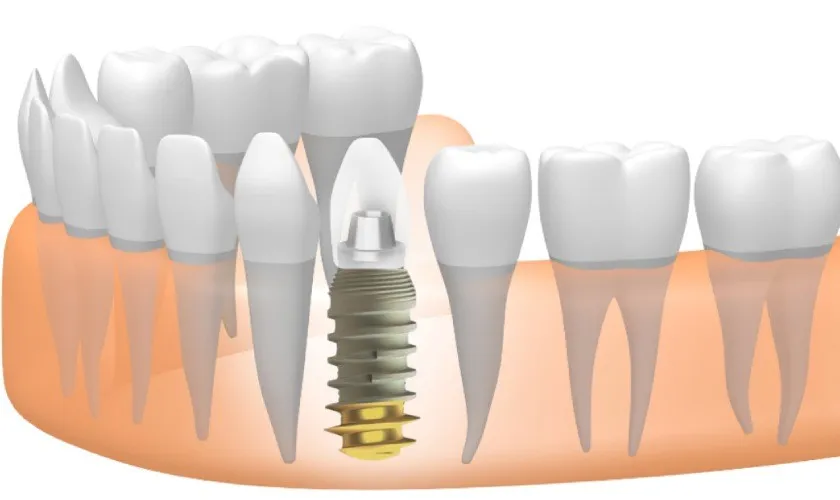

Trụ Implant có lẽ đã không còn quá xa lạ với lĩnh vực y khoa. Đây là một trong những giải pháp hữu ích cho hàm răng

Phương pháp trồng răng implant hiện nay đang được ưa chuộng. Đây là phương pháp mang đến hiệu quả rất cao cho những người muốn phục hình

Ngày nay, cấy ghép Implant được coi là phương pháp tốt nhất để phục hình hàm răng. Phương pháp cấy ghép Implant sử dụng trụ Implant cắm